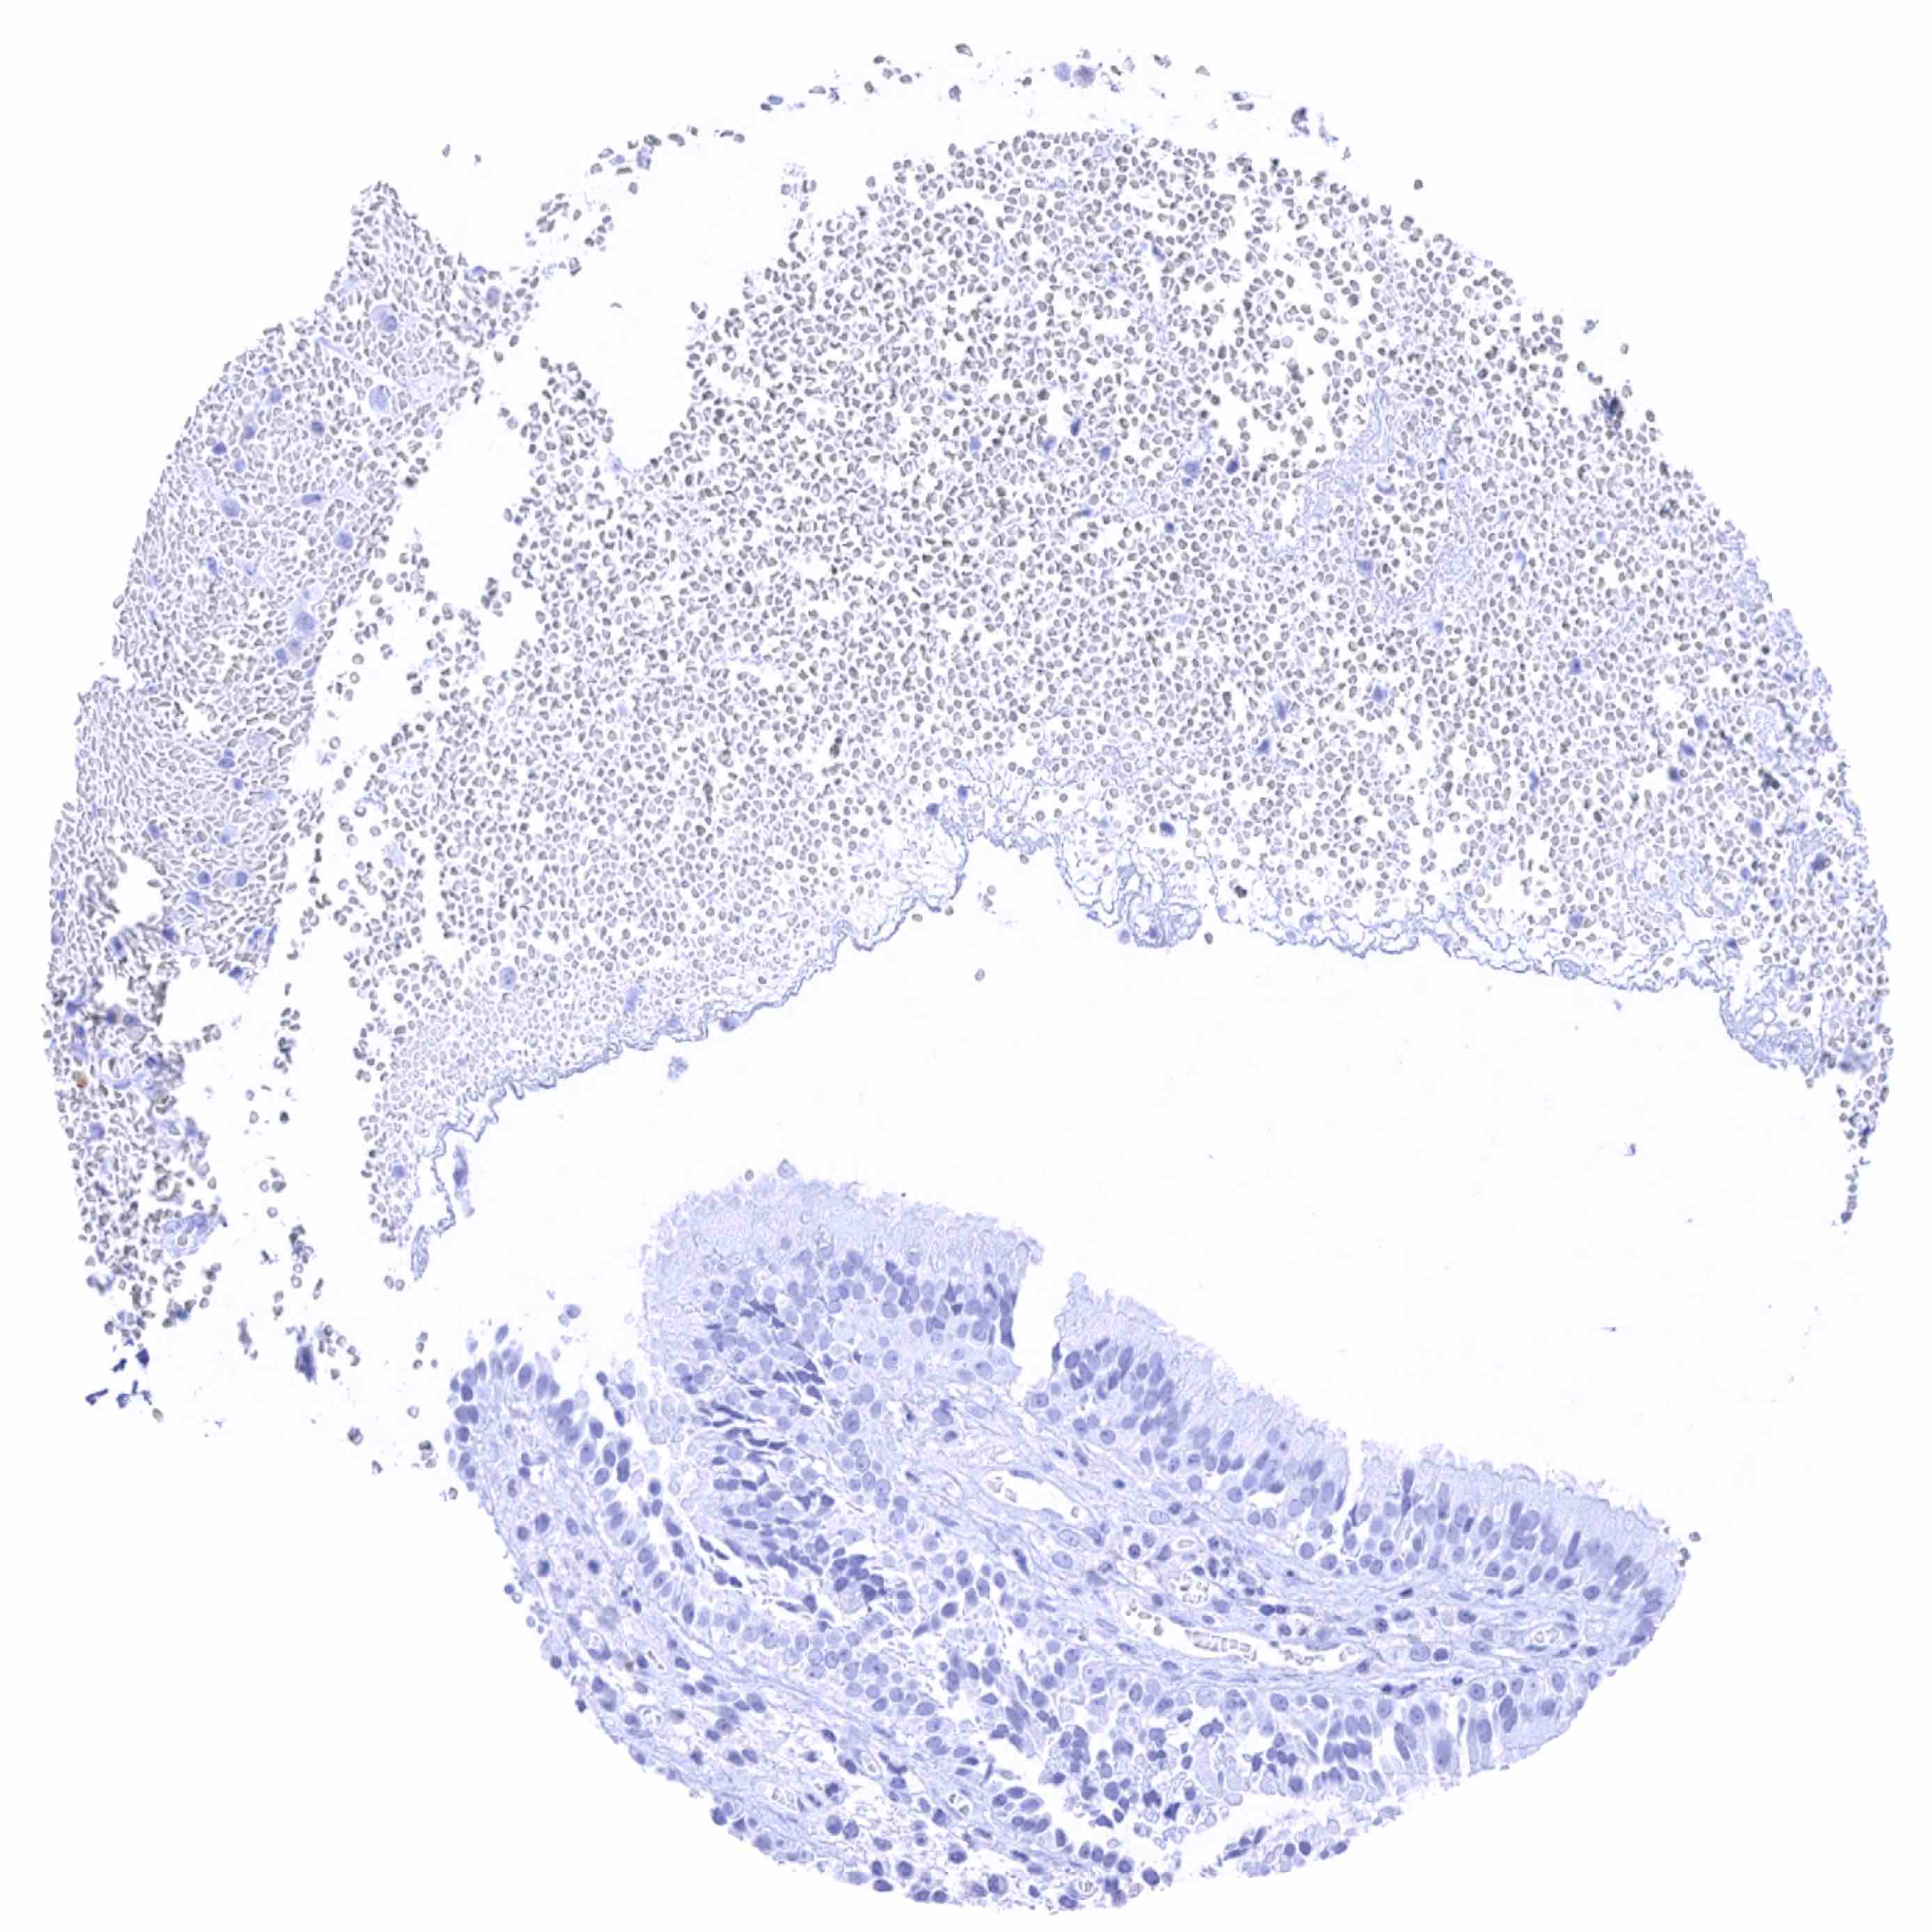

Tonsil, surface epithelium

Tonsil